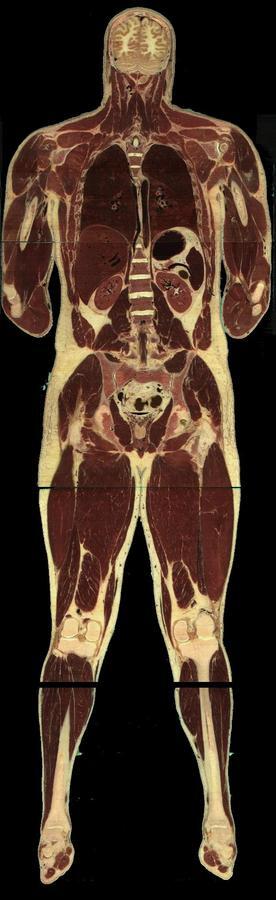

Un homme et une femme ont donné leur corps à la science et accepté d'être découpés après leur mort (l'homme était un condamné à mort américain....).

Les coupes anatomiques réalisées tous les millimètres pour l'homme, tous les 1/3 de millimètre pour la femme ont été numérisées et tout internaute peut appeler n'importe quelle coupe (axiale, coronale ou saggitale).

Bien évidemment, on n'a pas fait trois coupes (question pratique qui vient tout de suite à l'esprit des élèves !) mais une seule, axiale. Les coupes coronales et parasagittales ont été obtenues par reconstitution (d'où la présence parfois de bandes ou de décalages).

Coupes anatomiques d'un homme ou d'une femme

Vous pourrez choisir entre homme et femme et entre tête et corps entier.